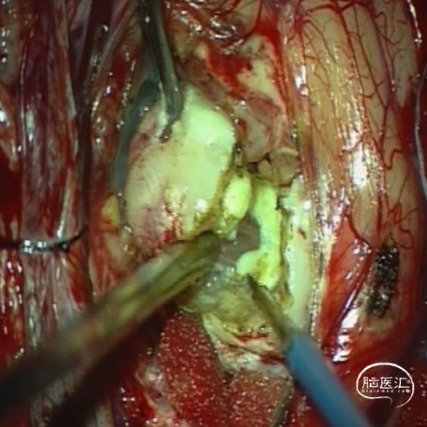

本例患儿肿瘤位于双侧额顶叶,大脑镰旁,增强扫描呈明显环形强化,提示肿瘤血运丰富。患儿年龄小,体重低,相对血容量少,如何控制术中出血是手术成功的关键。而术后肢体瘫痪或瘫痪加重是手术的主要并发症,中央沟静脉损伤、胼周动脉损伤、中央沟局部皮层损伤、癫痫、血肿以及脑水肿加重是其常见原因。术前脑血管造影有助于判断肿瘤与周围血管、组织的位置关系,明确上失状窦有无闭塞,对手术的切口设计有重要的参考价值及避免术中损伤不易发现的血管及组织。

本例患者术前脑血管造影提示瘤体主要由双侧大脑前动脉终末分支供血,造影静脉期瘤体显影明显,因此我们选择先采用神经介入技术超选部分主要供瘤动脉予弹簧圈栓塞,减少瘤体的供血。之后再行开颅探查双侧额顶叶占位性病变切除术。

(颅内巨大肿瘤)HE形态结合免疫组化结果符合非典型畸胎瘤/横纹肌样瘤(AT/RT),WHO IV级。

术后患儿神志清楚,言语流利,四肢活动可,无明显神经功能受损表现。